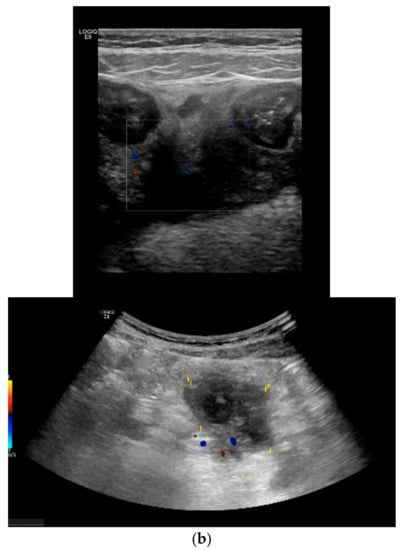

Depending of the CD phenotype, different ultrasonographic characteristics can be identified. The presence of ulcers can be visualized as depressions in the mucosal layer. Strictures are characterized by wall thickening with a narrowed lumen, with or without a dilatation of the proximal loop (pre-stenotic dilatation) (see Figure 5). The fistulae are seen as hypoechoic peri-intestinal areas with diameter < 2 cm with or without internal gaseous artifacts. Abdominal abscesses are seen as hypo-anechoic lesions containing fluid and gaseous artifacts, posterior enhancement, irregular margins sometimes within hypertrophic mesentery, without vascular signals at color Doppler (see Figure 6). An inflammatory mass is seen as an irregular hypoechogenic lesion, with vascular signals at color Doppler.

Figure 5.

Detection of complications: stricture with pre-stenotic dilation: Strictures are characterized by a wall thickening with a narrowed lumen, with or without a dilatation of the proximal loop (pre-stenotic dilatation).

Figure 6.

Detection of complications: fistulae and abscesses: (a) The fistulae are seen as hypoechoic peri-intestinal areas with a diameter <2 cm with or without internal gaseous artifacts. (b) Abdominal abscesses are seen as hypo-anechoic lesions containing fluid and gaseous artifacts, posterior enhancement, irregular margins sometimes within fibro-fatty proliferation, without vascular signals in color Doppler.